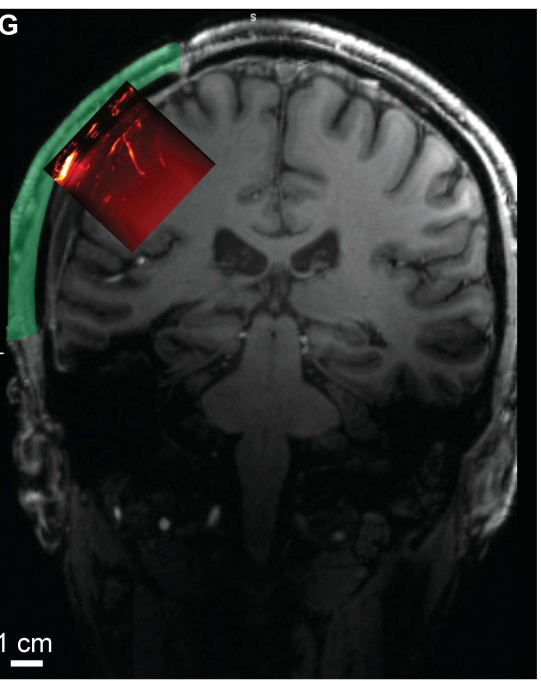

功能性超声成像平面与解剖学MRI扫描。

图片来源:《科学·转化医学》